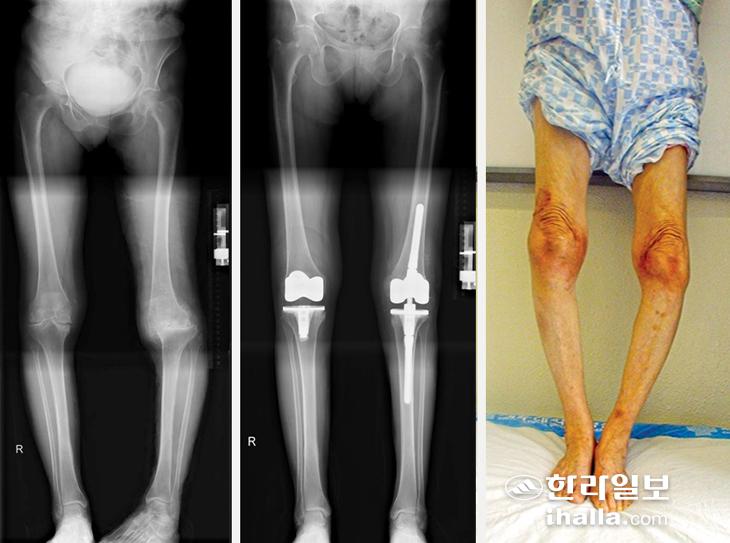

슬관절 퇴행성 관절염에서 시행할 수 있는 대표적인 수술방법으로는 크게 근위 경골 절골술과 인공관절 전치환술이 있는데, 70세 이상의 말기 퇴행성 관절염 환자에서 일반적으로 인공관절 전치환술을 시행하게 된다. 인공관절 수술이란 손상된 무릎 관절을 제거하고, 금속과 특수 플라스틱으로 제작된 인공 관절로 대체하는 수술이다. 수술 후에는 통증이 크게 줄고, 일상생활 기능도 상당 부분 회복된다.

로봇 수술은 수술 전 CT를 통해 환자의 무릎 상태를 3차원으로 정밀 분석한 뒤, 환자 개개인에 맞춰 수술 계획을 세우면, 로봇 시스템이 수술 중 절삭 범위와 위치를 실시간으로 가이드하면서 인공관절수술 시, 로봇 팔의 도움을 받는 수술이다. 즉, 모든 과정을 로봇이 하는 것이 아니라, 수술 부위 절개, 연부조직 제거 등은 의사들이 시행 후, 뼈의 절삭을 로봇이 하게 된다.

로봇 인공관절 수술의 장점은 ▷보다 정확한 절삭 및 정렬 ▷수술전 계획에 따른 수술 진행으로 정확한 인공관절의 삽입 ▷개개인에 맞춘 맞춤형 수술이 가능하다는 것이다. 단점으로는 기존 수술보다 수술 시간이 다소 길어질 수 있고, 좀 더 큰 절개가 필요하며, 많은 비용의 부담이 필요하다. 이러한 단점들은 향후 과학의 발전을 통한 비용 절감 및 시술 시간을 단축으로 조만간 해결되리라 사료된다.